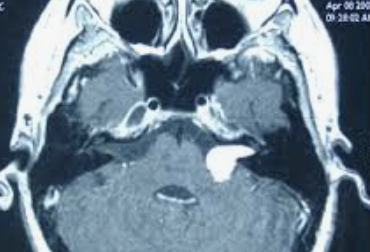

Tumeur nerveuse bénigne développée aux dépens du nerf acoustique, encore appelée schwannome, car elle naît précisément des cellules de la gaine du nerf, les cellules de Schwann.